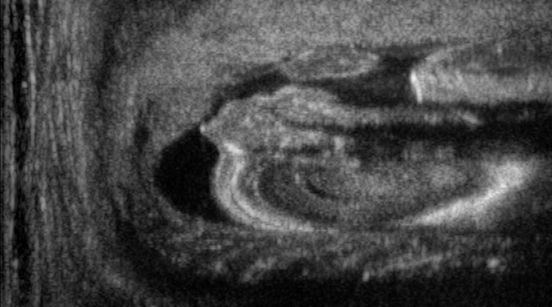

We train each learning-based network (custom-WDSR) with 1.5K images, where the input is the outcome of the selected up-sampling method (i.e., Cubic convolution), and the target is the original high-resolution image. Indeed, input and target images have the same resolution, as the reconstruction of the missing lines has been already performed by Cubic convolution. Figs. 3, 4, and 5 show the results of the network prediction, compared with the input and the target images. Target images correspond to spatial high-resolution images; input images are the outcome of the up-sampling interpolation, which is applied to spatial low-resolution images (i.e., the down-sampling along the lateral direction of high-resolution images); prediction images represent the output of the neural network.

Our framework visually improves the results, in terms of blurring and artefacts. This result is more evident in the magnification of the ear of the foetus (Fig. 3), the mitral valve (Fig. 4), and the mass edges (Fig. 5). Fig. 6 shows the error image of the three anatomical districts with both 2X and 4X up-sampling factors, with the maximum error in the scale . The error is more evident in the contours of the anatomical structures; moreover, the abdominal district shows a smaller error than the cardiac and obstetric ones. We underline that the view for each image is scaled to its maximum, to improve the visualisation of the error.